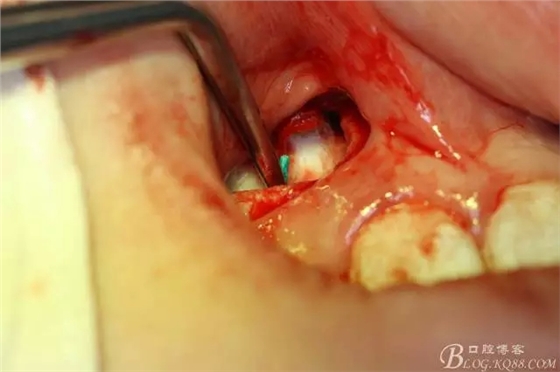

病例資料: 患者、柴xx、女、16歲。??茩z查及病歷如下圖: 患者同意我院正畸科建議,遂轉(zhuǎn)診倒外科。術(shù)前簽知情同意書。 治療過程: 圖1.術(shù)前的CBCT檢查:13阻生,疑為含牙囊腫。縱剖面顯示12牙根吸收至根尖1/3。 圖2.局部麻醉下 。行唇側(cè)弧形切口,12松動不到1°。 圖3.翻瓣、暴露骨面。 圖4.去骨、 暴露13牙冠 圖5.去骨、逐漸顯露13。 圖7.拔除13. 圖8.摘除囊壁 圖9.必須完整剝離囊壁。 圖10.摘除囊壁后形成的骨腔 圖11.超聲骨刀12根尖倒預(yù)備 圖13. 消毒棉球骨腔內(nèi)隔濕血液,紙尖干燥倒預(yù)備好的根管 圖14. 紙尖無血即可 圖15。MTA倒充填 圖16.骨腔填塞膠原蛋白海綿 圖17.拔除的13及摘除的囊壁 圖18.縫合 圖19.術(shù)后x線根尖片影像:MTA封閉根尖